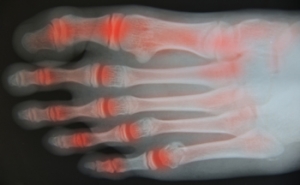

Managing Flare-Ups of Foot Arthritis

Foot arthritis is a condition where the joints in the foot become inflamed, leading to stiffness, swelling, and pain. It may result from wear and tear, autoimmune diseases, or injury. Flare-ups can be triggered by overexertion, stress, infection, or changes in activity, often causing increased joint pain and reduced mobility. These episodes may disrupt daily life and make walking or standing uncomfortable. A podiatrist can help manage symptoms through customized treatment plans, supportive footwear, orthotics, and lifestyle guidance. If you are experiencing ongoing joint pain in your feet, it is suggested that you consult a podiatrist who can provide effective relief and management techniques.

Arthritic Foot Care

Arthritis is a joint disorder that involves the inflammation of different joints in your body, such as those in your feet. Arthritis is often caused by a degenerative joint disease and causes mild to severe pain in all affected areas. In addition to this, swelling and stiffness in the affected joints can also be a common symptom of arthritis.

In many cases, wearing ill-fitting shoes can worsen the effects and pain of arthritis. Wearing shoes that have a lower heel and extra room can help your feet feel more comfortable. In cases of rheumatoid arthritis, the arch in your foot may become problematic. Buying shoes with proper arch support that contour to your feet can help immensely.

Alleviating Arthritic Pain

- Exercises that stretch the foot can prevent further pain and injury and increase mobility

- Most of the pain can be alleviated with anti-inflammatory drugs, heat, and topical medications

- Massages can help temporarily alleviate pain.

It is best to see your doctor for the treatment that is right for your needs and symptoms. Conditions vary, and a podiatrist can help you determine the right method of care for your feet.

Arthritic Foot Care

During your lifetime, you will probably walk about 75,000 miles, which is quite a lot of stress to put on your feet. As you get older, the 26 bones and 30 joints in each of your feet will lose flexibility and elasticity. Your foot’s natural shock absorbers will wear down as well. Having arthritis added to this mix only makes matters worse. Your joints will become distorted and inflamed, which is why arthritic foot care needs to be something to think about every day.

When dealing with arthritis, having additional foot complications, such as bunions, hammertoes, or neuroma, can be a serious detriment. To avoid these, buy well-fitting shoes with a lower heel and good support. Arthritis causes you to lose your arch, so having shoes with good arch support is also highly recommended.

Aside from getting good arch support, the shoes need to fit comfortably and properly as well. A good place to start is by leaving a finger width between the back of the shoe and your foot to gauge proper size. It is also helpful to have a square or rounded toe box in the front to provide even more comfort. Another thing to look for is a rubber sole that can provide a cushion and absorb shock as you walk. This adds flexibility to the ball of your foot when you push off your heel to walk.

Exercise is another key aspect of arthritic foot care. Exercise not only strengthens and stretches your muscles and joints, but helps to prevent further injury and pain as well. Stretching the Achilles tendon, the tendon located in the back of your heel, will give you added mobility and reduce pain due to stress. Another thing you can do is massage your feet, kneading the ball of your foot as well as your toes from top to bottom.

Stretching the Achilles tendon is a simple exercise that you can do at home anytime. Lean against the wall with your palms flat against the surface while placing one foot forward, towards the wall, and one foot behind you. Bend your forward knee towards the wall while keeping your back knee locked straight, and make sure both your heels are completely touching the ground at all times. This will stretch your Achilles tendon and calf muscles as well. You will feel the stretch almost immediately. You can also stretch your toes in a couple ways. One involves taking a rubber band and wrapping it around both your big toes while your heels remain together. Then, pull them apart to stretch your big toe. You can also place a rubber band around all the toes of one of your feet. Then, try to separate each individual toe, stretching them all.

A final step you can take to help your arthritis is taking non-steroid, non-inflammatory drugs or topical medicines with capsaicin. Unfortunately, there is no complete way to remove all of your arthritic pain. However, following some of this advice can go a long way in staying as pain-free as possible.